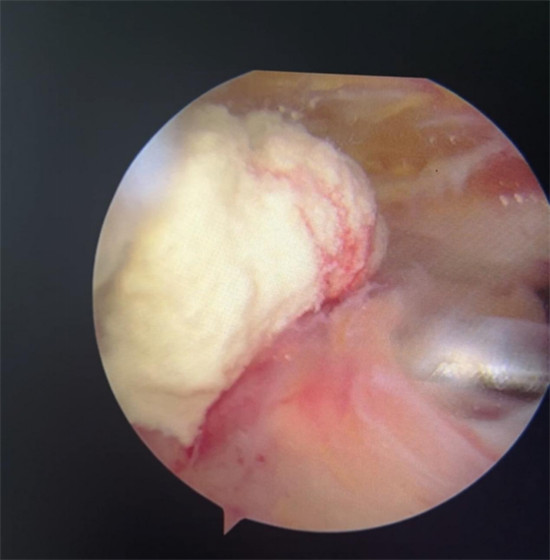

賀大媽慕名來廣安醫(yī)院找羅軍主任就診,面對羅醫(yī)生,賀大媽哭訴:“羅醫(yī)生,我真想剁下自己的這只胳膊。”羅軍主任根據(jù)患者的癥狀拍片,診斷為岡上肌鈣化性肌腱炎,隨后,羅醫(yī)生為李大媽進行了肩關(guān)節(jié)鏡微創(chuàng)手術(shù),竟從她的右肩“擠”出“牙膏”。

鈣化性肌腱炎是一種自限性疾病,就是疾病發(fā)生發(fā)展到一定程度后,經(jīng)長期機體調(diào)節(jié)能夠控制病情發(fā)展并逐漸恢復(fù)痊愈。它分為四個階段:鈣化前期、鈣化形成期、鈣化吸收期、鈣化后期,往往在“鈣鹽斑塊”吸收時,疼痛最劇烈,賀大媽就正處于“吸收期”。

是不是只要病人撐得住,讓鈣鹽吸收就沒事了?羅軍主任表示,經(jīng)保守治療無法緩解或病程長的患者,應(yīng)盡早采取手術(shù)治療。而且,部分患者鈣鹽無法完全吸收,拖下去只會使病情惡化,造成肩膀肩袖肌腱的損傷。